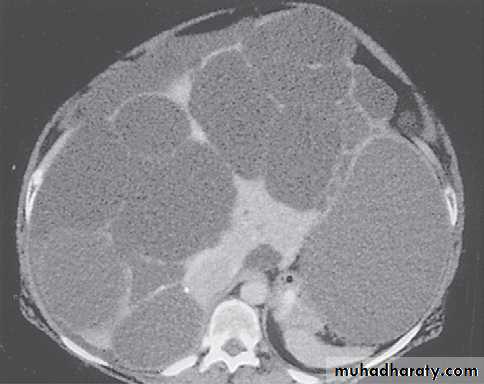

MRI images of kidneys. A Normal kidneys. B Polycystic kidneys; although the kidney enlargement is extreme, this patient had only slightlyreduced GFR.

Markedly enlarged polycystic kidneys in comparison to a normal kidney in the middle.

polycystic liver disease. A, a very large, cyst. B several large cysts. C, multiple smaller cysts